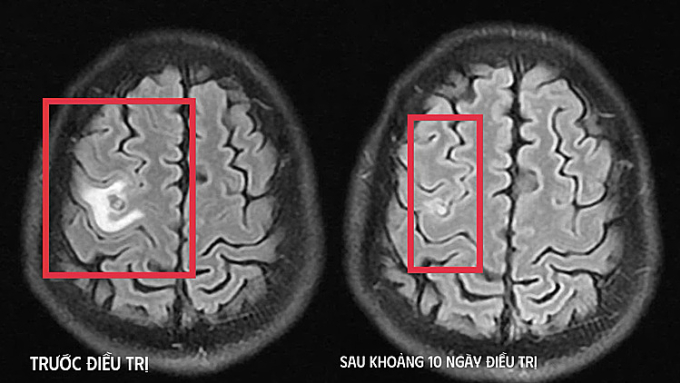

Bác sĩ chụp cộng hưởng từ (MRI) sọ não, phát hiện tổn thương dạng nang nhỏ tại thùy trán trái, xung quanh có phù não nhẹ. Hình ảnh này hướng nhiều đến tổn thương do ký sinh trùng hơn là u não nguyên phát. Người bệnh tiếp tục được chỉ định xét nghiệm, kết quả dương tính sán dây chó. Bác sĩ chẩn đoán tổn thương não do ký sinh trùng, điều trị nội khoa theo phác đồ, kết hợp kiểm soát triệu chứng và theo dõi sát diễn biến thần kinh. Sau khoảng 10 ngày, tình trạng bệnh nhân cải thiện rõ rệt.

Hình ảnh chụp chiếu trước và sau khi điều trị. Ảnh: Bệnh viện cung cấp